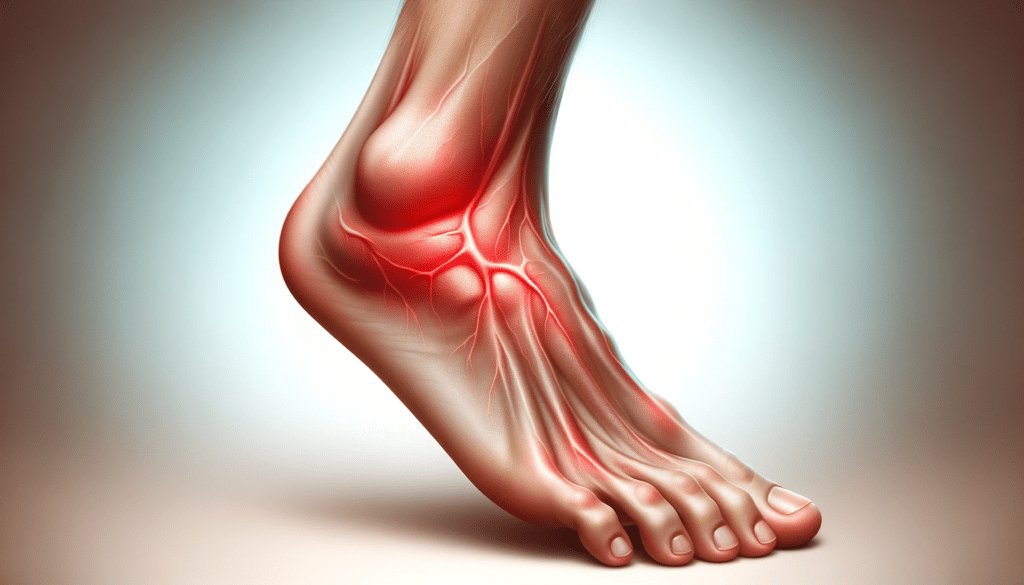

Se você já sentiu seu pé inchado e doendo, sabe o quanto isso pode ser desconfortável.

Embora o inchaço e a dor possam ser causados por várias coisas, é preciso entender as principais causas e o que você pode fazer para aliviar os sintomas.

Causas do pé inchado e doendo

Seus pés podem ficar inchados e doloridos por várias razões. Algumas causas são inofensivas e podem ser tratadas em casa, enquanto outras exigem atenção médica imediata.

Aqui estão algumas das causas mais comuns de pé inchado e doendo:

O pé inchado e doendo pode ser causado por uma variedade de fatores, desde condições inofensivas até doenças graves.

Sintomas Relacionados

Quando você está com o pé inchado e doendo, é possível que outros sintomas também apareçam.

Alguns dos sintomas mais comuns incluem dor, vermelhidão, dificuldade em movimentar ou apoiar o pé, sensação de peso nas pernas, cansaço ou falta de ar.